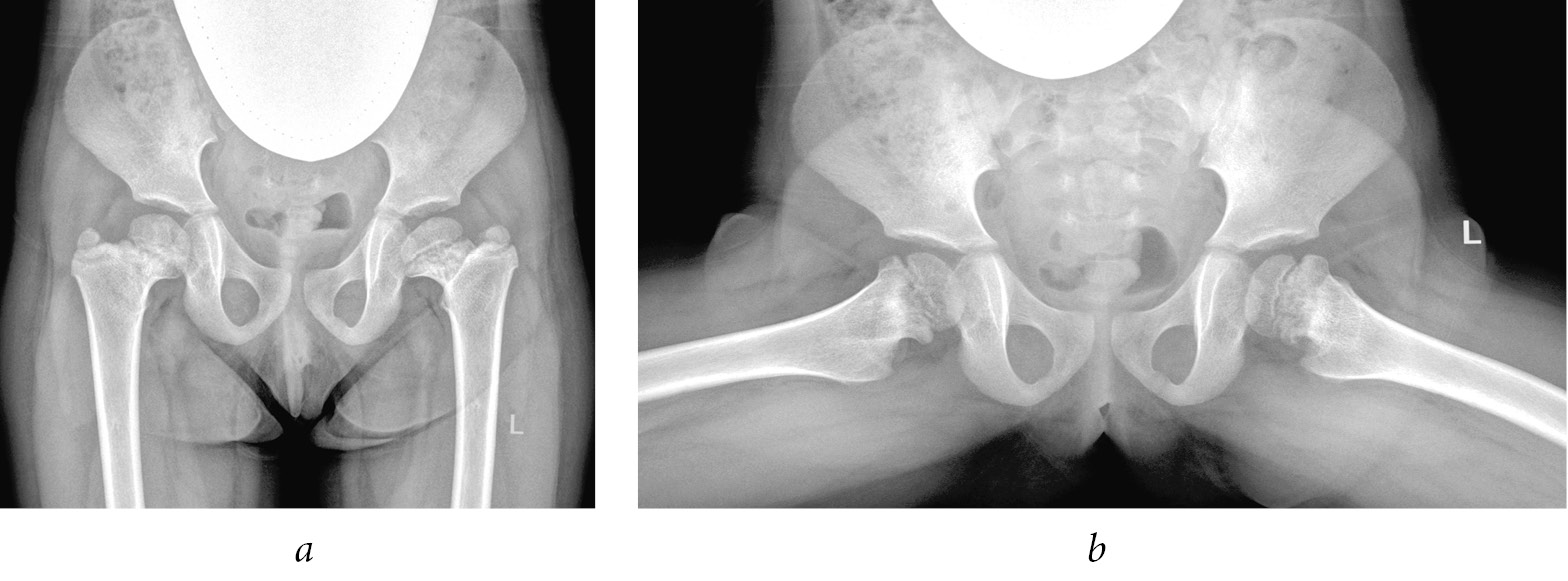

- other reasons were noted in 5 (1.3%) of all the patients. These patients had an unspecified or rare cause of lesions of the hip joints, such as that resulting from the use of extracorporeal membrane oxygenation method in the neonatal period [13] (Fig. 5).

Fig. 5. Radiographs of patient G. at the age of 4 years: frontal view (a) and Lauenstein view (b). The emerging high position of the greater trochanter on both sides and dystrophic changes in the femoral neck are visible. A radiograph taken when the patient was 3 years of age had shown manifestations of transient synovitis of the hip joints after an acute respiratory viral infection